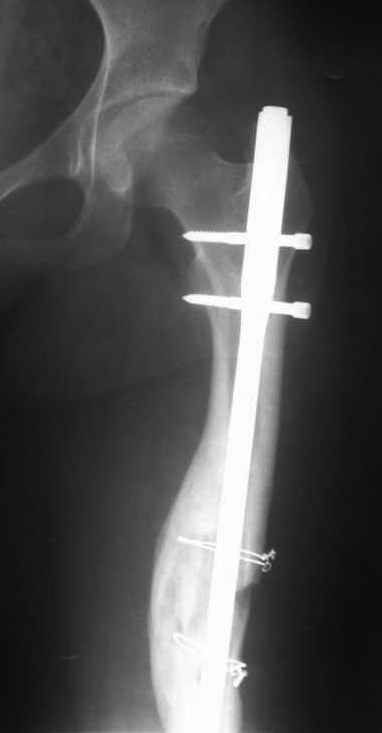

В нашей работе мы столкнулись с похожей ситуацией. У девушки 16-ти лет произошел изгиб интрамедуллярного штифта с вторичным смещением отломков бедра (гвоздь оказался тонковат, использовали, видимо, по принципу, что было под рукой). Вот только укорочение последнего составило 4см. Оперировали с обнажением места перелома, удлинили бедро на штифте ChM с элементами костной аутоплатики а-ля Хахутов. К слову, это был один из первых опытов использования нами БИОС вообще. Исходный результат - полная косолидация и выигрыш 3см, что расцениваем его как достойный данного изложения.